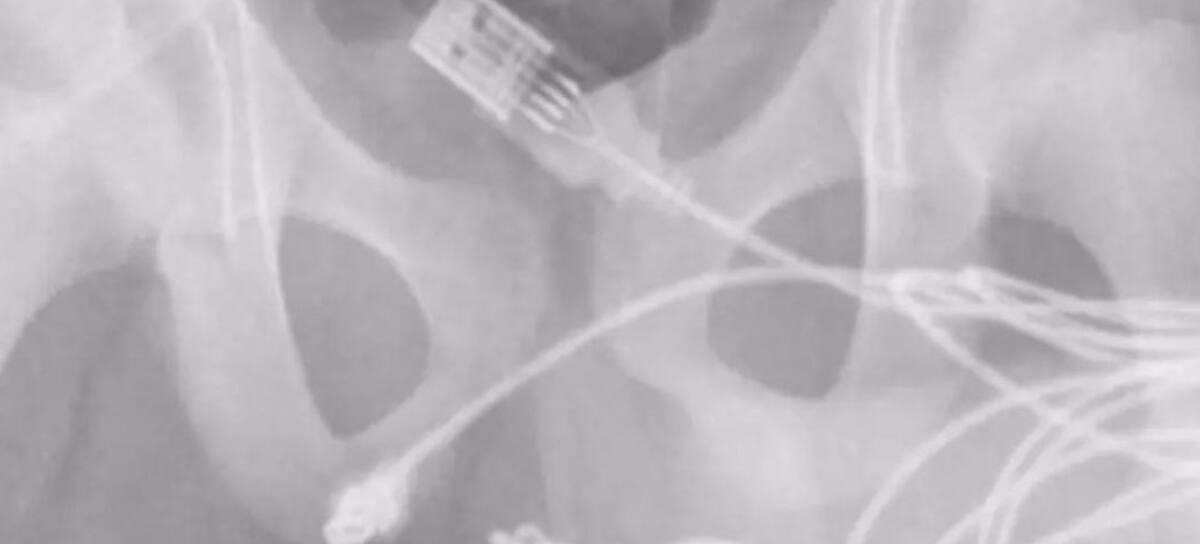

Para quitarle el cable en cuestión, tuvo que ser atendido en un complejo procedimiento que consistía en extraerle un fragmento de cable para terminar con el puerto principal del USB en el interior del miembro.